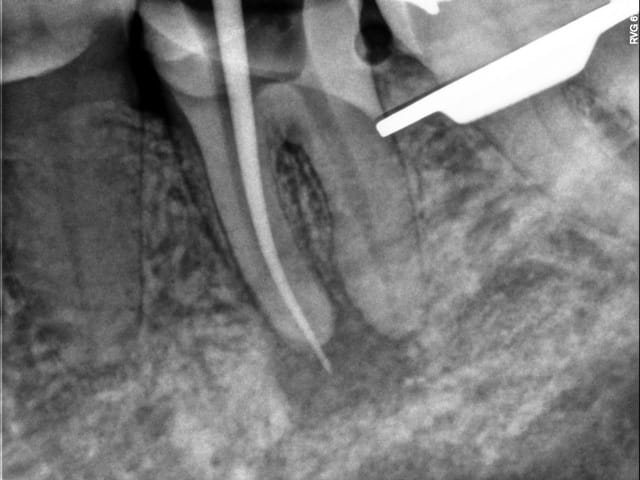

Un cas comme chipoudine le recommande (posé ce matin) : Pas de fêlure donc overlay, avec un petit tenon fibré... Des trucs qu'on ne peut pas faire en France...ou en ayant une certaine patientèle peut-être... C'est triste.

PS: Légère extrusion de pâte en distal, j'ai un peu forcé sur le Mac Spadden, faut que je m'équipe du système B...

Pourquoi un tenon ici, et pas directement ton onlay?

Tu vires pas la 8?